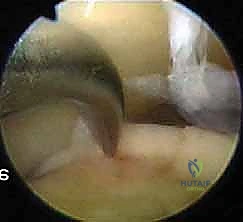

* FIG 6 • Arthroscopic view of the ankle joint.

2. Diagnostic Arthroscopy and Lesion Characterization

Now that we're in, let's perform a systematic diagnostic arthroscopy.

* Initial Survey: Systematically visualize the entire joint: the tibial plafond, medial and lateral gutters, talar dome, and the anterior and posterior aspects of the joint. Look for synovitis, loose bodies, impingement lesions (soft tissue or bony), and any associated pathology.

* Locating the OLT: Our preoperative MRI indicated a medial talar dome lesion. We'll use a probing hook to precisely locate and characterize it.

* Assess the size (length and width).

* Evaluate the depth of the cartilage defect.

* Determine the stability of the surrounding cartilage and the lesion itself. Use the probe to gently push on the lesion. Is it soft? Is it delaminated? Is there an intact cartilage surface over a subchondral cyst?

* Our current patient has a Stage III lesion, meaning the articular cartilage is breached, and we expect to find synovial fluid between the fragment and the underlying subchondral bone. This is ideal for microfracture.